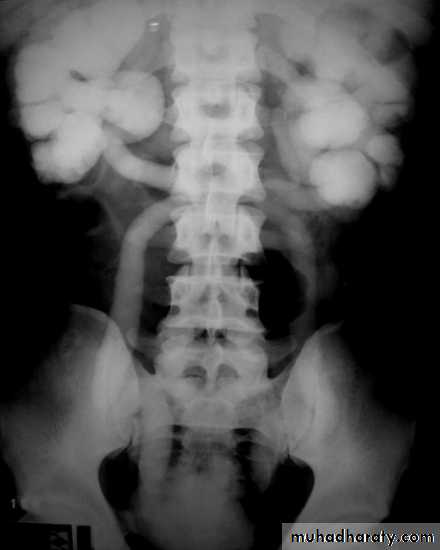

High density renal stonesStage horn calculus KUB filmsradio opaque stones